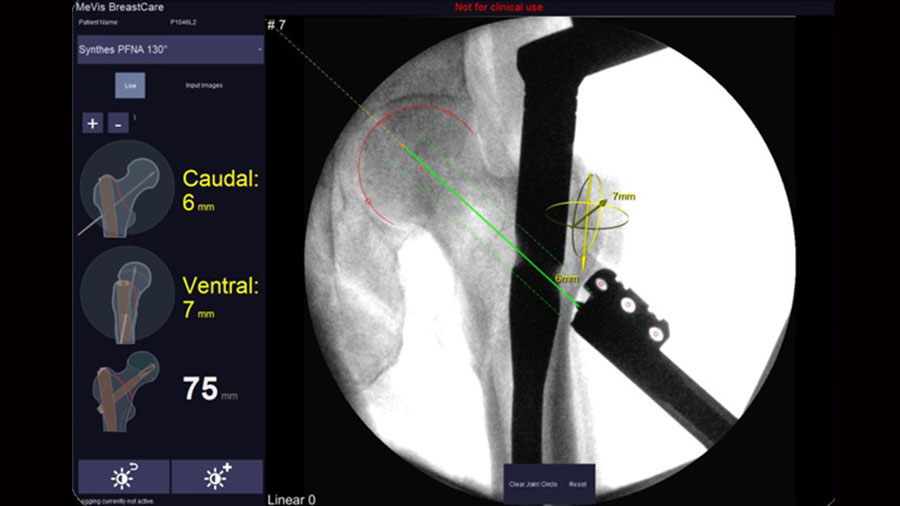

X-in-One: Placing implants safe and sound

The task of placing implants plays a key role in trauma and orthopedics surgery. Current solutions for computer aided surgery lack of wider acceptance due to considerable disadvantages regarding complexity, costs, and effectiveness.

Proposed solution

A simplified computer aided surgery system X-in-One has been developed* utilizing a conventional C-arm as imaging and navigation means rendering additional tracking and imaging equipment obsolete. The system provides simple integration into standard clinical routine and strong potential for improving clinical practice for a variety of surgical interventions in trauma and orthopedics.

*Graphical User Interface in collaboration with Mevis Medical AG